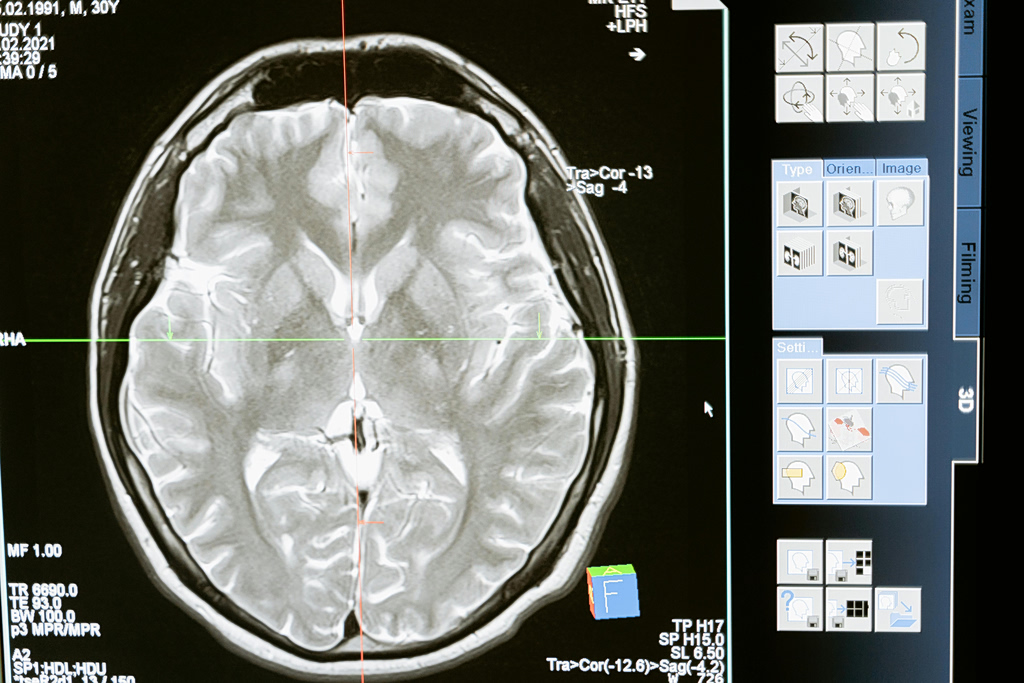

Μπορεί η βιταμίνη D να «φρενάρει» τη φθορά του εγκεφάλου;

Τα υψηλότερα επίπεδα βιταμίνης D στο αίμα κατά τη μέση ηλικία σχετίζονται με χαμηλότερα επίπεδα της πρωτεΐνης Ταυ στον εγκέφαλο, που σχετίζεται με τη νόσο Αλτσχάιμερ, χρόνια αργότερα. Αυτό διαπιστώνει μελέτη, που δημοσιεύθηκε στο περιοδικό της Αμερικανικής Ακαδημίας Νευρολογίας «Neurology Open Access». Στη μελέτη συμμετείχαν 793 άτομα με μέσο όρο ηλικίας τα 39 έτη, που […]